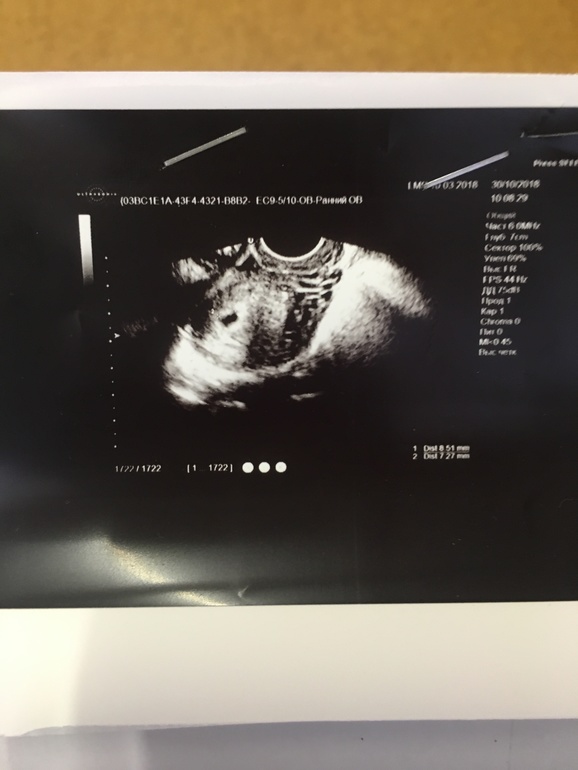

Отписываюсь. По УЗИ все в порядке, увеличен правый яичник ибо там была овуляция и там ЖТ, нигде второго яйца нет. Но вот сейчас опять выделения начались, уже более яркие. А по УЗИ с ПЯ все в порядке.. что это ума не приложу